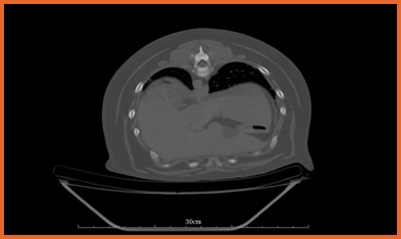

我們提供留院服務並擁有相應的治療設施,亦是小數備有CT電腦掃描及MRI磁力共振等大型醫療儀器的診所及醫院。